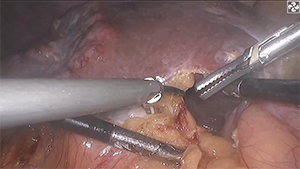

荧光腹腔镜引导的肝脏解剖性S8v+S4切除术

作者:张雯雯 | 作者单位:解放军第一医学中心